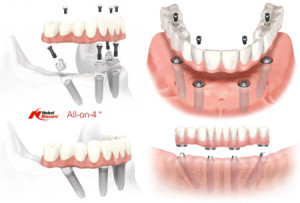

Имплантация зубов по технике «все на 4-ех» на верхнюю и нижнюю челюсти

Среди прочего, Вы можете воспользоваться стоматологической хирургией по технике «Все-на-4», которая также производится в нашей стоматологической клинике в Венгрии. Общая стоимость реконструкции полного рта (нижняя и верхняя челюсть) может обойтись Вам около 11,500 Евро. Будьте добры, вопрос о точной стоимости имплантации обеих челюстей узнать в клинике. Если у Вас отсутствуют все коренные зубы, в таком случае для поддержки имплантатов понадобится цельный мост или же протез для их замены, после чего Вы будете сиять своей новой, здоровой улыбкой! Зубные имплантаты заменят Ваши прежние зубы и в некотором случае послужат заменой корней. Здесь цены гарантированно ниже среднестатистических цен Ирландских клиник!

Среди прочего, Вы можете воспользоваться стоматологической хирургией по технике «Все-на-4», которая также производится в нашей стоматологической клинике в Венгрии. Общая стоимость реконструкции полного рта (нижняя и верхняя челюсть) может обойтись Вам около 11,500 Евро. Будьте добры, вопрос о точной стоимости имплантации обеих челюстей узнать в клинике. Если у Вас отсутствуют все коренные зубы, в таком случае для поддержки имплантатов понадобится цельный мост или же протез для их замены, после чего Вы будете сиять своей новой, здоровой улыбкой! Зубные имплантаты заменят Ваши прежние зубы и в некотором случае послужат заменой корней. Здесь цены гарантированно ниже среднестатистических цен Ирландских клиник!